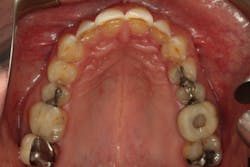

From the two-dimensional evaluation, the signs of occlusal instability were clear. Darren had very thin, chipping incisal edges, to the point where they were becoming transparent. The patient had almost worn shelves into the lingual of the maxillary anteriors, suggesting a restricted envelope of function. He also had wear into dentin in the anterior teeth as well as posterior teeth, and his anterior teeth had Class 1 mobility.

In addition, Darren failed The Dawson Academy’s five requirements of occlusal stability:

- Stable and equal intensity stops on all teeth in centric relation

- Anterior guidance in harmony with the envelope of function

- All posterior teeth disclude during mandibular protrusive movement

- All posterior teeth disclude on the nonworking side during mandibular lateral movement

- All posterior teeth disclude on the working side during mandibular lateral movement

Luckily, the patient was a Piper TMJ Classification 1 with healthy intact joint assembly. His functional problems were primarily occlusal-muscle. But the dentition also exhibited signs of acid corrosion in a presentation that suggested gastroesophageal reflux disease (GERD), so we referred Darren to his physician where he was treated for GERD prior to starting any dental treatment.